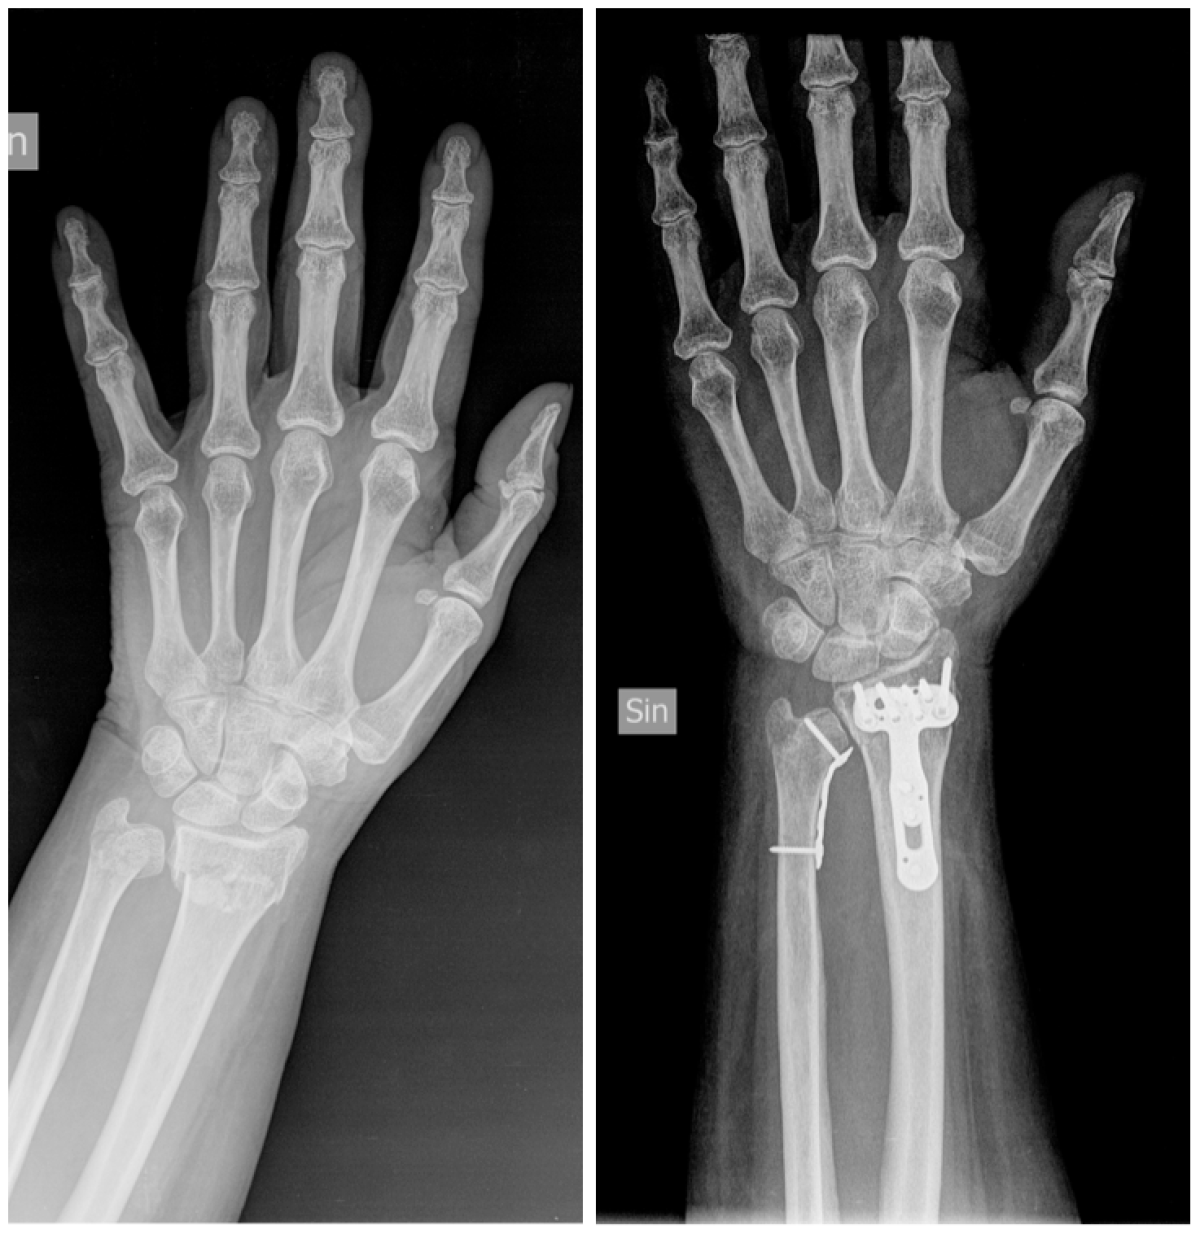

Frattura epifisi distale radio: esami

Il principale strumento diagnostico per verificare il tipo di frattura dell’estremo distale è la radiografica, attraverso proiezioni antero-posteriore e laterale.

Tramite radiografia, è possibile acquisire informazioni relativamente alla stabilità della lesione e trarne adeguate indicazioni per il trattamento.

Sono cinque le misurazioni radiografiche consigliate per valutare fratture dell’estremità distale del radio:

- inclinazione palmare;

- inclinazione radiale;

- lunghezza del radio;

- larghezza del radio;

- variazione ulnare.

In caso di traumi in pazienti giovani e attivi, alla radiografia vengono affiancate TAC e RMN, per permettere al medico di individuare un trattamento più idoneo al caso.

- riduzione a cielo aperto e sintesi con placca;